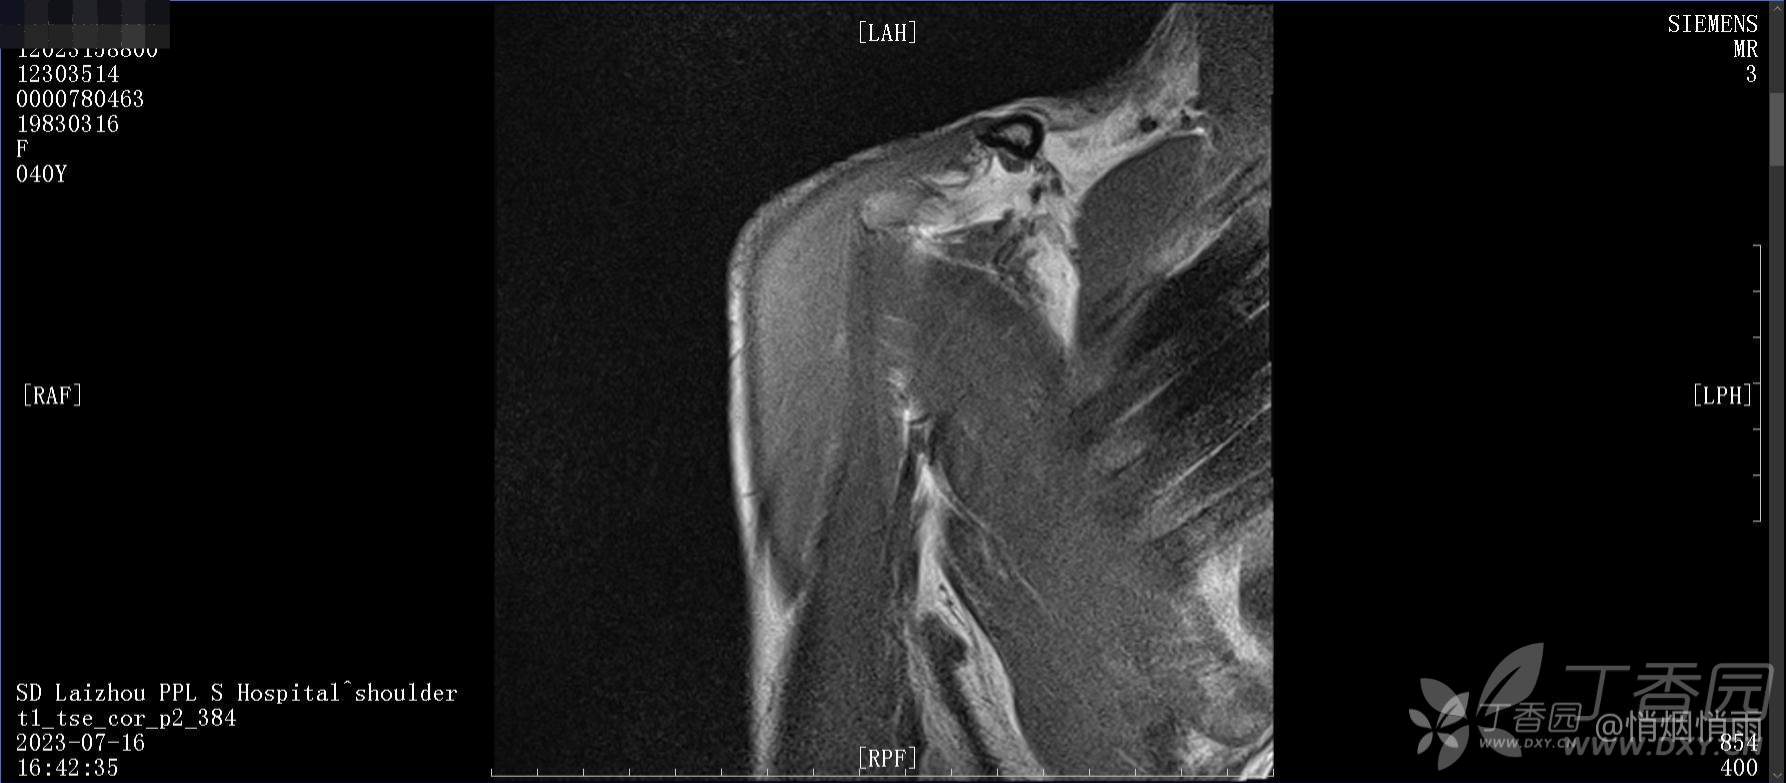

查体:右肩关节局部轻度肿胀,肩胛区压痛明显,痛处不固定,肩关节痛性活动受限,jobe test(+),lift -off test(+),中指、环指感觉较余指减退,余肢端感觉及血运情况可。

目前的诊断,暂时依据辅助检查诊为肩袖损伤,但是患者疼痛的性质和特点,却不是单纯的肩袖损伤所致。考虑过胸廓出口综合征,但是该疾病会出现肩胛区的疼痛吗?(由于考虑到费用的问题,没再进行下一步的检查)带状疱疹会有如此的症状吗?